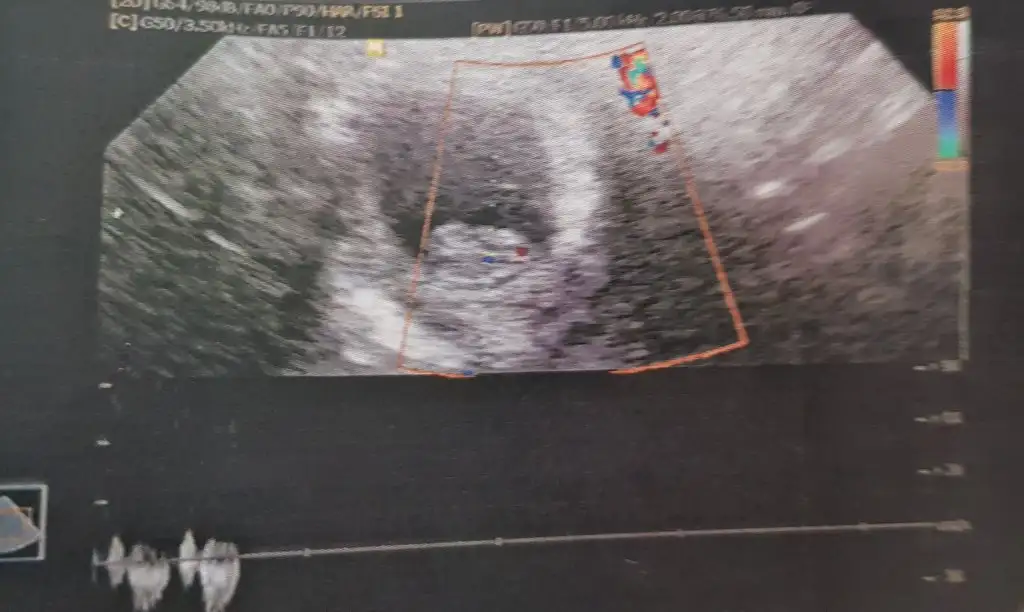

Arkadaşlar lütfen babada bakın kız mı erkek mi çok merak ediyorum 10haftalik bu resimde

Eklentiler

• 15832202238201395352965.webp

15832202238201395352965.webp

29,1 KB · Görüntüleme: 79